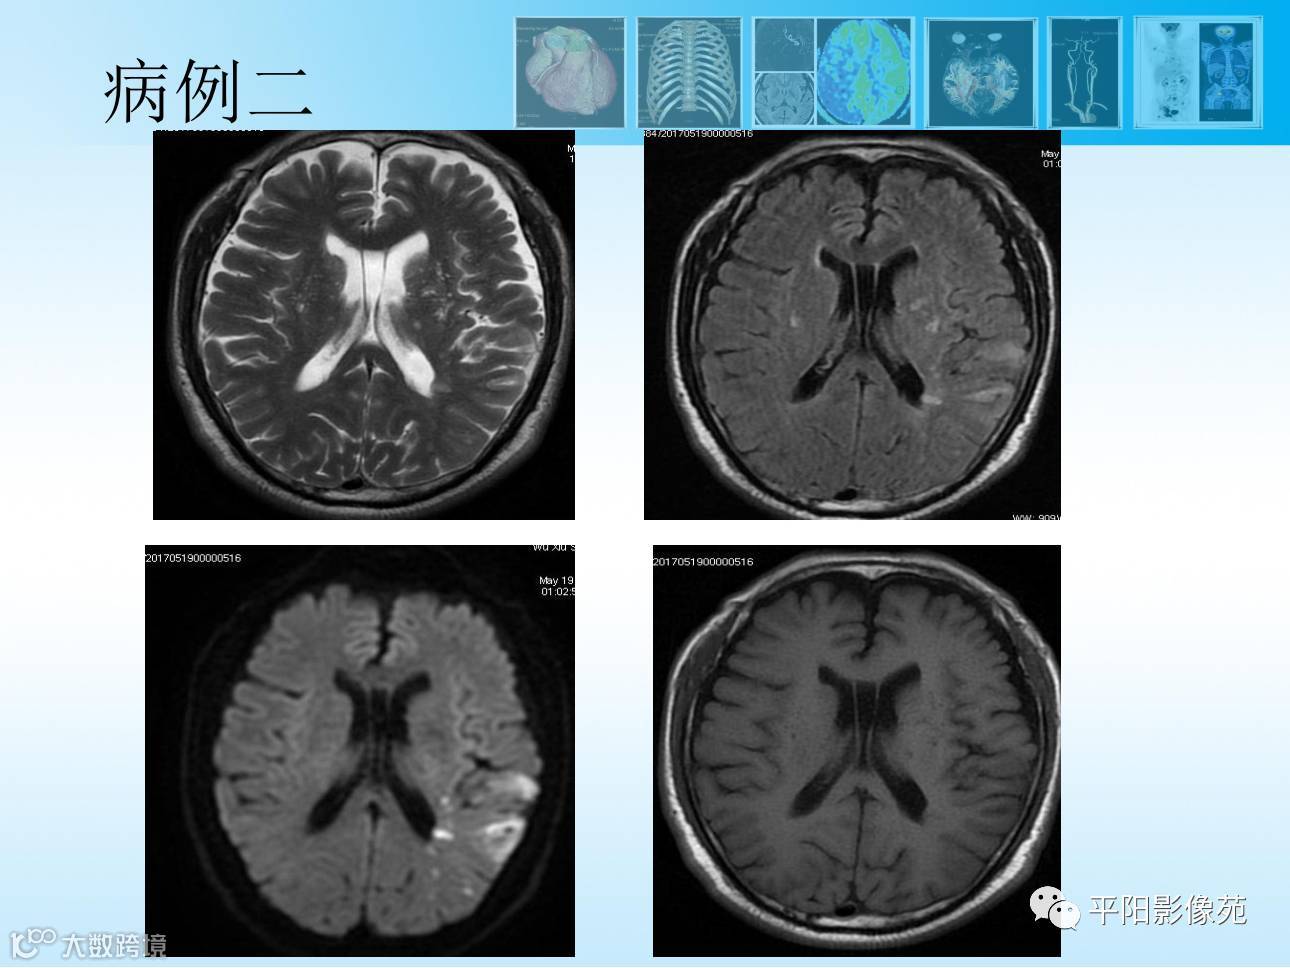

【MR功能成像专题2】3D-ASL灌注成像篇

导读:动脉自旋标记ASL成像,是一种完全无创的、不需注射造影剂的灌注成像方法,临床应用广泛。